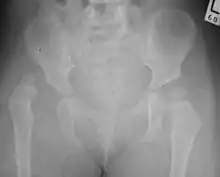

Hip dysplasia can be diagnosed by ultrasound[42] and projectional radiography ("X-ray").[43] Ultrasound imaging is generally preferred at up to 4 months due to limited ossification of the femoral head up until then, and is the most accurate method for imaging of the hip during the first few months after birth. However, in most instances, ultrasound screening should not be performed before 3 to 4 weeks of age because of the normal physiologic laxity.[44][notes 1] When universal with targeted ultrasound screening was compared, the former results in an insignificant reduction in the late diagnosis of hip dysplasia, which is why universal ultrasonographic screening of newborn infants is not recommended by the American Academy of Pediatrics.[11]

Despite the widespread use of ultrasound, pelvis X-ray is still frequently used to diagnose or monitor hip dysplasia or for assessing other congenital conditions or bone tumors.[45]